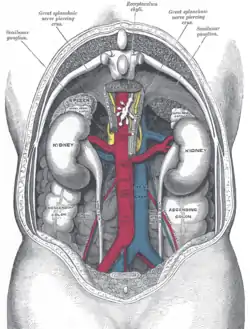

The abdominal cavity contains most organs of the digestive system, including the stomach, the small intestine, and the colon with its attached appendix. Other digestive organs are known as the accessory digestive organs and include the liver, its attached gallbladder, and the pancreas, and these communicate with the rest of the system via various ducts. The spleen, and organs of the urinary system including the kidneys, and adrenal glands also lie within the abdomen, along with many blood vessels including the aorta and inferior vena cava. The urinary bladder, uterus, fallopian tubes, and ovaries may be seen as either abdominal organs or as pelvic organs. Finally, the abdomen contains an extensive membrane called the peritoneum. A fold of peritoneum may completely cover certain organs, whereas it may cover only one side of organs that usually lie closer to the abdominal wall. This is called the retroperitoneum, and the kidneys and ureters are known as retroperitoneal organs.

View of the various organs and blood-vessels in proximity with liver.

View of the various organs and blood-vessels in proximity with liver. The relations of the viscera and large vessels of the abdomen, seen from behind.

The relations of the viscera and large vessels of the abdomen, seen from behind.